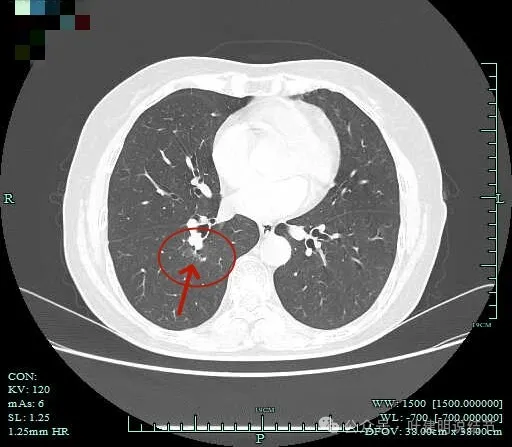

病灶出现,淡磨玻璃密度,但轮廓较清,且表面不平。

病灶内部有走行的支气管,但显得有些僵硬;病灶表面有浅分叶。

灶内血管走行,轮廓与边界清楚。